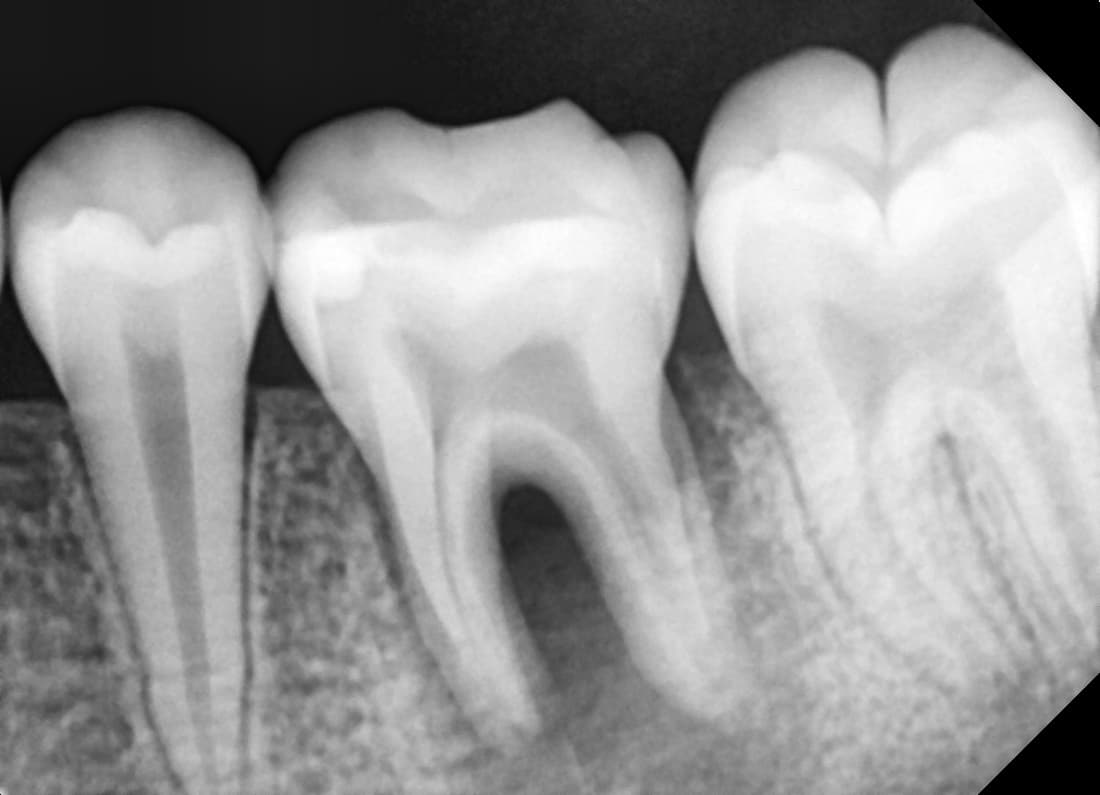

Root Canal Re-treatment

Molar recurrence after treatment elsewhere

Before

After

Complete healing 1 year 9 months after finding additional canal through re-treatment